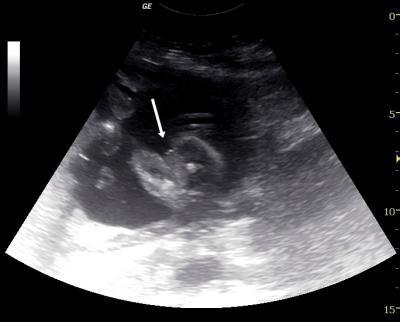

Hallöchen :) Hab hier ein Bild aus der 21.ssw. Doc sagt Mädel. Die 2 Striche sind wohl die Schamlippen!? Das Bild ist quasi von unten.. Rechts die Beinchen und dazwischen das Geschlecht. Ich bin mir unsicher... Hab auch jetzt oft gelesen, dass 2 Striche auch ein Junge sein können und 3 Striche eindeutig ein Mädel . Was meint ihr? Würde mich über Meinungen freuen :)

Ich meinte LINKS die Beine, sorry !

Hi, ich würde sagen, das ist ein Mädchen. Liebe Grüße Nicole